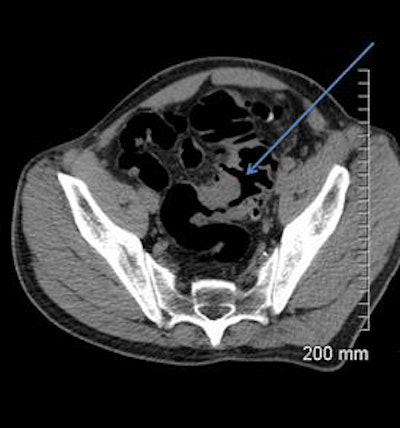

A 68-year-old woman with a fistula, categorized as C1D4E2, between the diverticular sigmoid and the vaginal vault. All images courtesy of Dr. John Hanson.